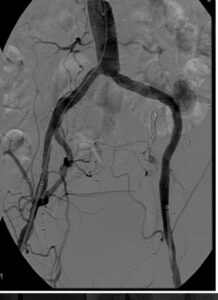

🔹 شواهد تصویری

در نمونههای ارائهشده، دو مورد از بیماران با پلاکهای ظاهراً گسترده در سیتیاسکن بررسی شدند.

اما پس از انجام آنژیوگرافی عروقی، مشخص گردید که:

-

لومن واقعی عروق بهطور قابل ملاحظهای باز است،

-

میزان انسداد کمتر از آن چیزی است که در سیتی دیده میشود،

-

و تصمیمگیری جراحی بر اساس یافتههای واقعی میتواند با اطمینان بیشتری انجام گیرد.

این موارد نمونهای از تفاوت بین برداشت تصویری ناشی از Blooming Artefact و واقعیت آناتومیک هستند.

تطبیق یافتههای بالینی (نبض، علائم ایسکمی) با داپلر و آنژیوگرافی، ضروری است.

در بیماران با پلاکهای کلسیفیه گزارششده ولی بدون علائم انسداد، باید پیش از کنار گذاشتن کاندیداتوری پیوند، بررسی دقیقتر از طریق آنژیوگرافی انجام شود.